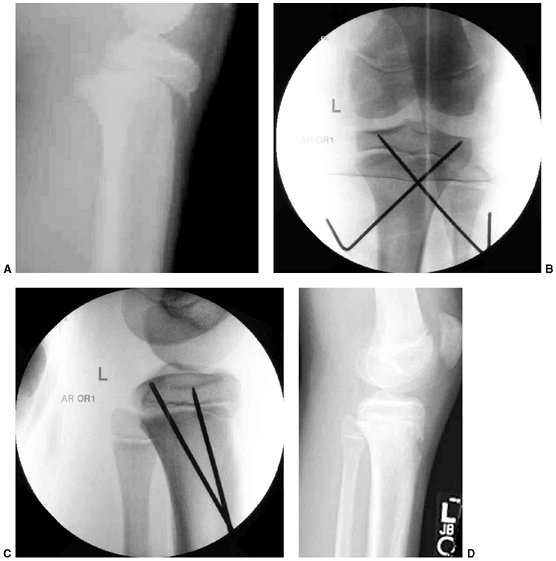

![]() |

Figure 33.17 Type II supracondylar humerus fracture with medial impaction and varus alignment. A, B:

Anteroposterior and lateral views of a type II supracondylar humerus fracture with medial impaction. Note that although there is little displacement on the lateral view, the Baumann angle is 0 degrees on the anteroposterior. C, D: Anteroposterior and lateral intraoperative views of the distal humerus after the impacted fracture was reduced and fixed with divergent lateral pins. Note that on the anteroposterior, the Baumann angle is restored, and on the lateral, the anterior humeral line intersects the capitellum. The reduction was maintained during the postoperative period. |